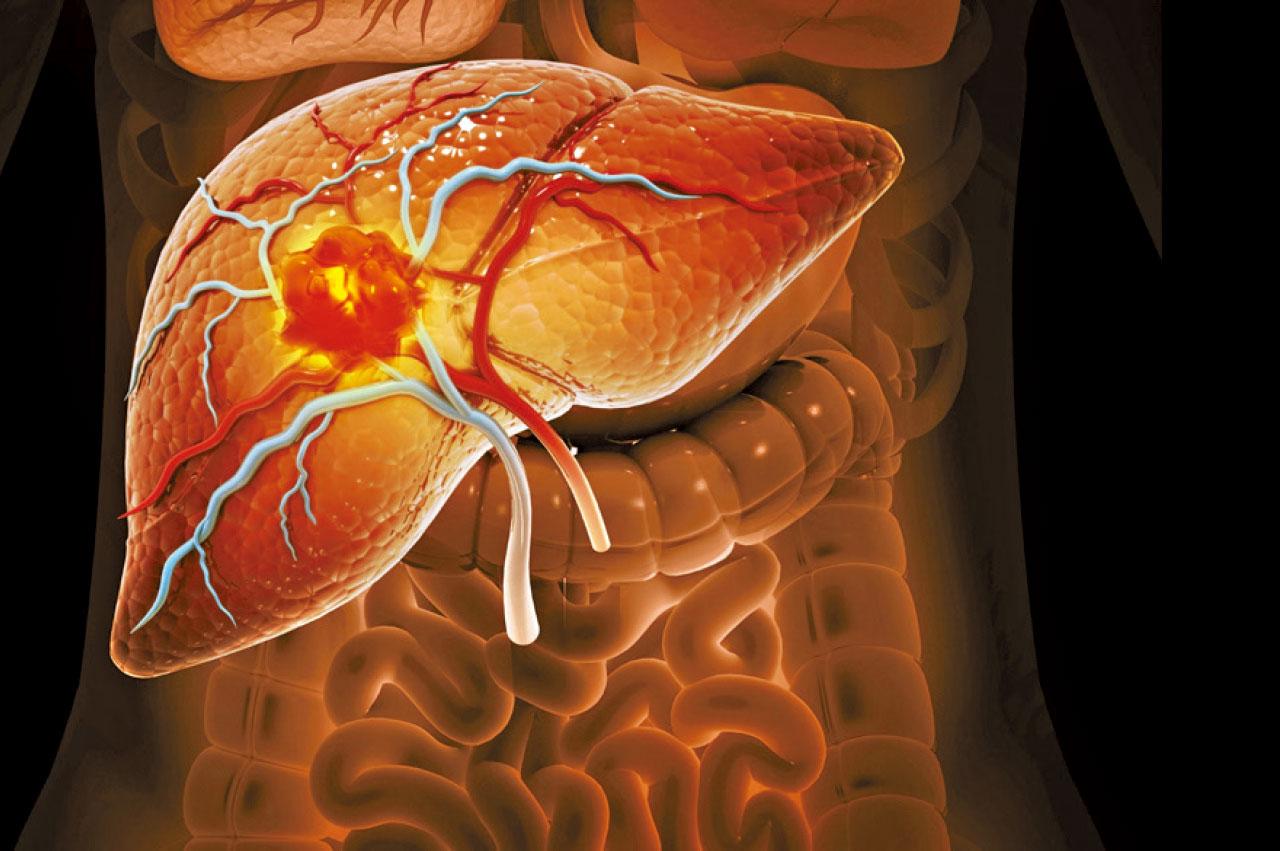

雖然慢性乙型肝炎未必會有任何徵狀,達成功能治癒亦未必有感覺,但在檢測的層面,功能治癒卻十分重要。黃麗虹解釋,「如果表面抗原檢測轉為陰性,代表日後併發症的風險大大降低。有很多研究,包括香港的研究都顯示,如果表面抗原為陰性,肝癌或肝硬化等併發症的風險減少一半以上,甚至減少達七至八成;有些文獻更指出,如果45歲前能夠達到功能治癒,其肝癌風險與一個從來沒有乙肝的人相若,等於因乙肝導致肝癌的風險已經逆轉或消失了。」

可是現有藥物較難做到功能治癒。黃麗虹指,現時乙肝治療藥物分兩大類,其一是口服抗病毒藥(核苷酸類藥物),可壓抑病毒複製,令血清裡的乙肝病毒載量(HBV DNA)減至測不到,惟表面抗原則變動不大;另一款藥物為干擾素,雖然可增加些少機率達到功能治癒,但副作用相對較多,基本上已不再用於治療乙肝。「若用口服抗病毒藥達到功能治癒,就不用再繼續終身服食核苷酸類藥物。我們相信其實是由病人本身的免疫系統清除病毒,而病人會持續用藥多6至12個月,方才停藥。發生機率大約為0.3%至0.5%。」

乙肝患者若未能減低HBsAg,將來仍有可能演化為肝硬化或肝癌。

幸而現時有不同類型的乙肝新藥正處於臨床研究階段,包括可減低表面抗原(ASO)、更深入的壓抑病毒複製,以及調節免疫系統清除病毒;幾種藥物可以單一使用,又或互相配合一同使用。「其中一款ASO藥物已進入第三期臨床測試階段。其原理是透過干擾乙肝病毒在細胞核中的複製過程,可以令表面抗原快速下降。」黃麗虹說,「第一、二期研究數據顯示可令部分患者達到功能治癒,而第三期研究有超過1,000個參加者,香港也有不少中心參與,結果相信可於2026年上半年公布,若結果理想,有望於2027年可在香港使用。」